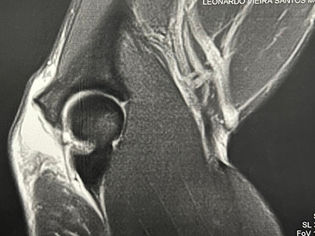

Remplissage no Tratamento da Instabilidade Anterior do Ombro

Remplissage é uma palavra francesa que significa "preencher". No âmbito ortopédico, refere-se a uma técnica cirúrgica.

Caso Clínico de Prótese Reversa: Fratura de Úmero Proximal Head Split

A prótese reversa tem se mostrado uma solução eficaz nesses casos, oferecendo melhor estabilidade e funcionalidade ao ombro.